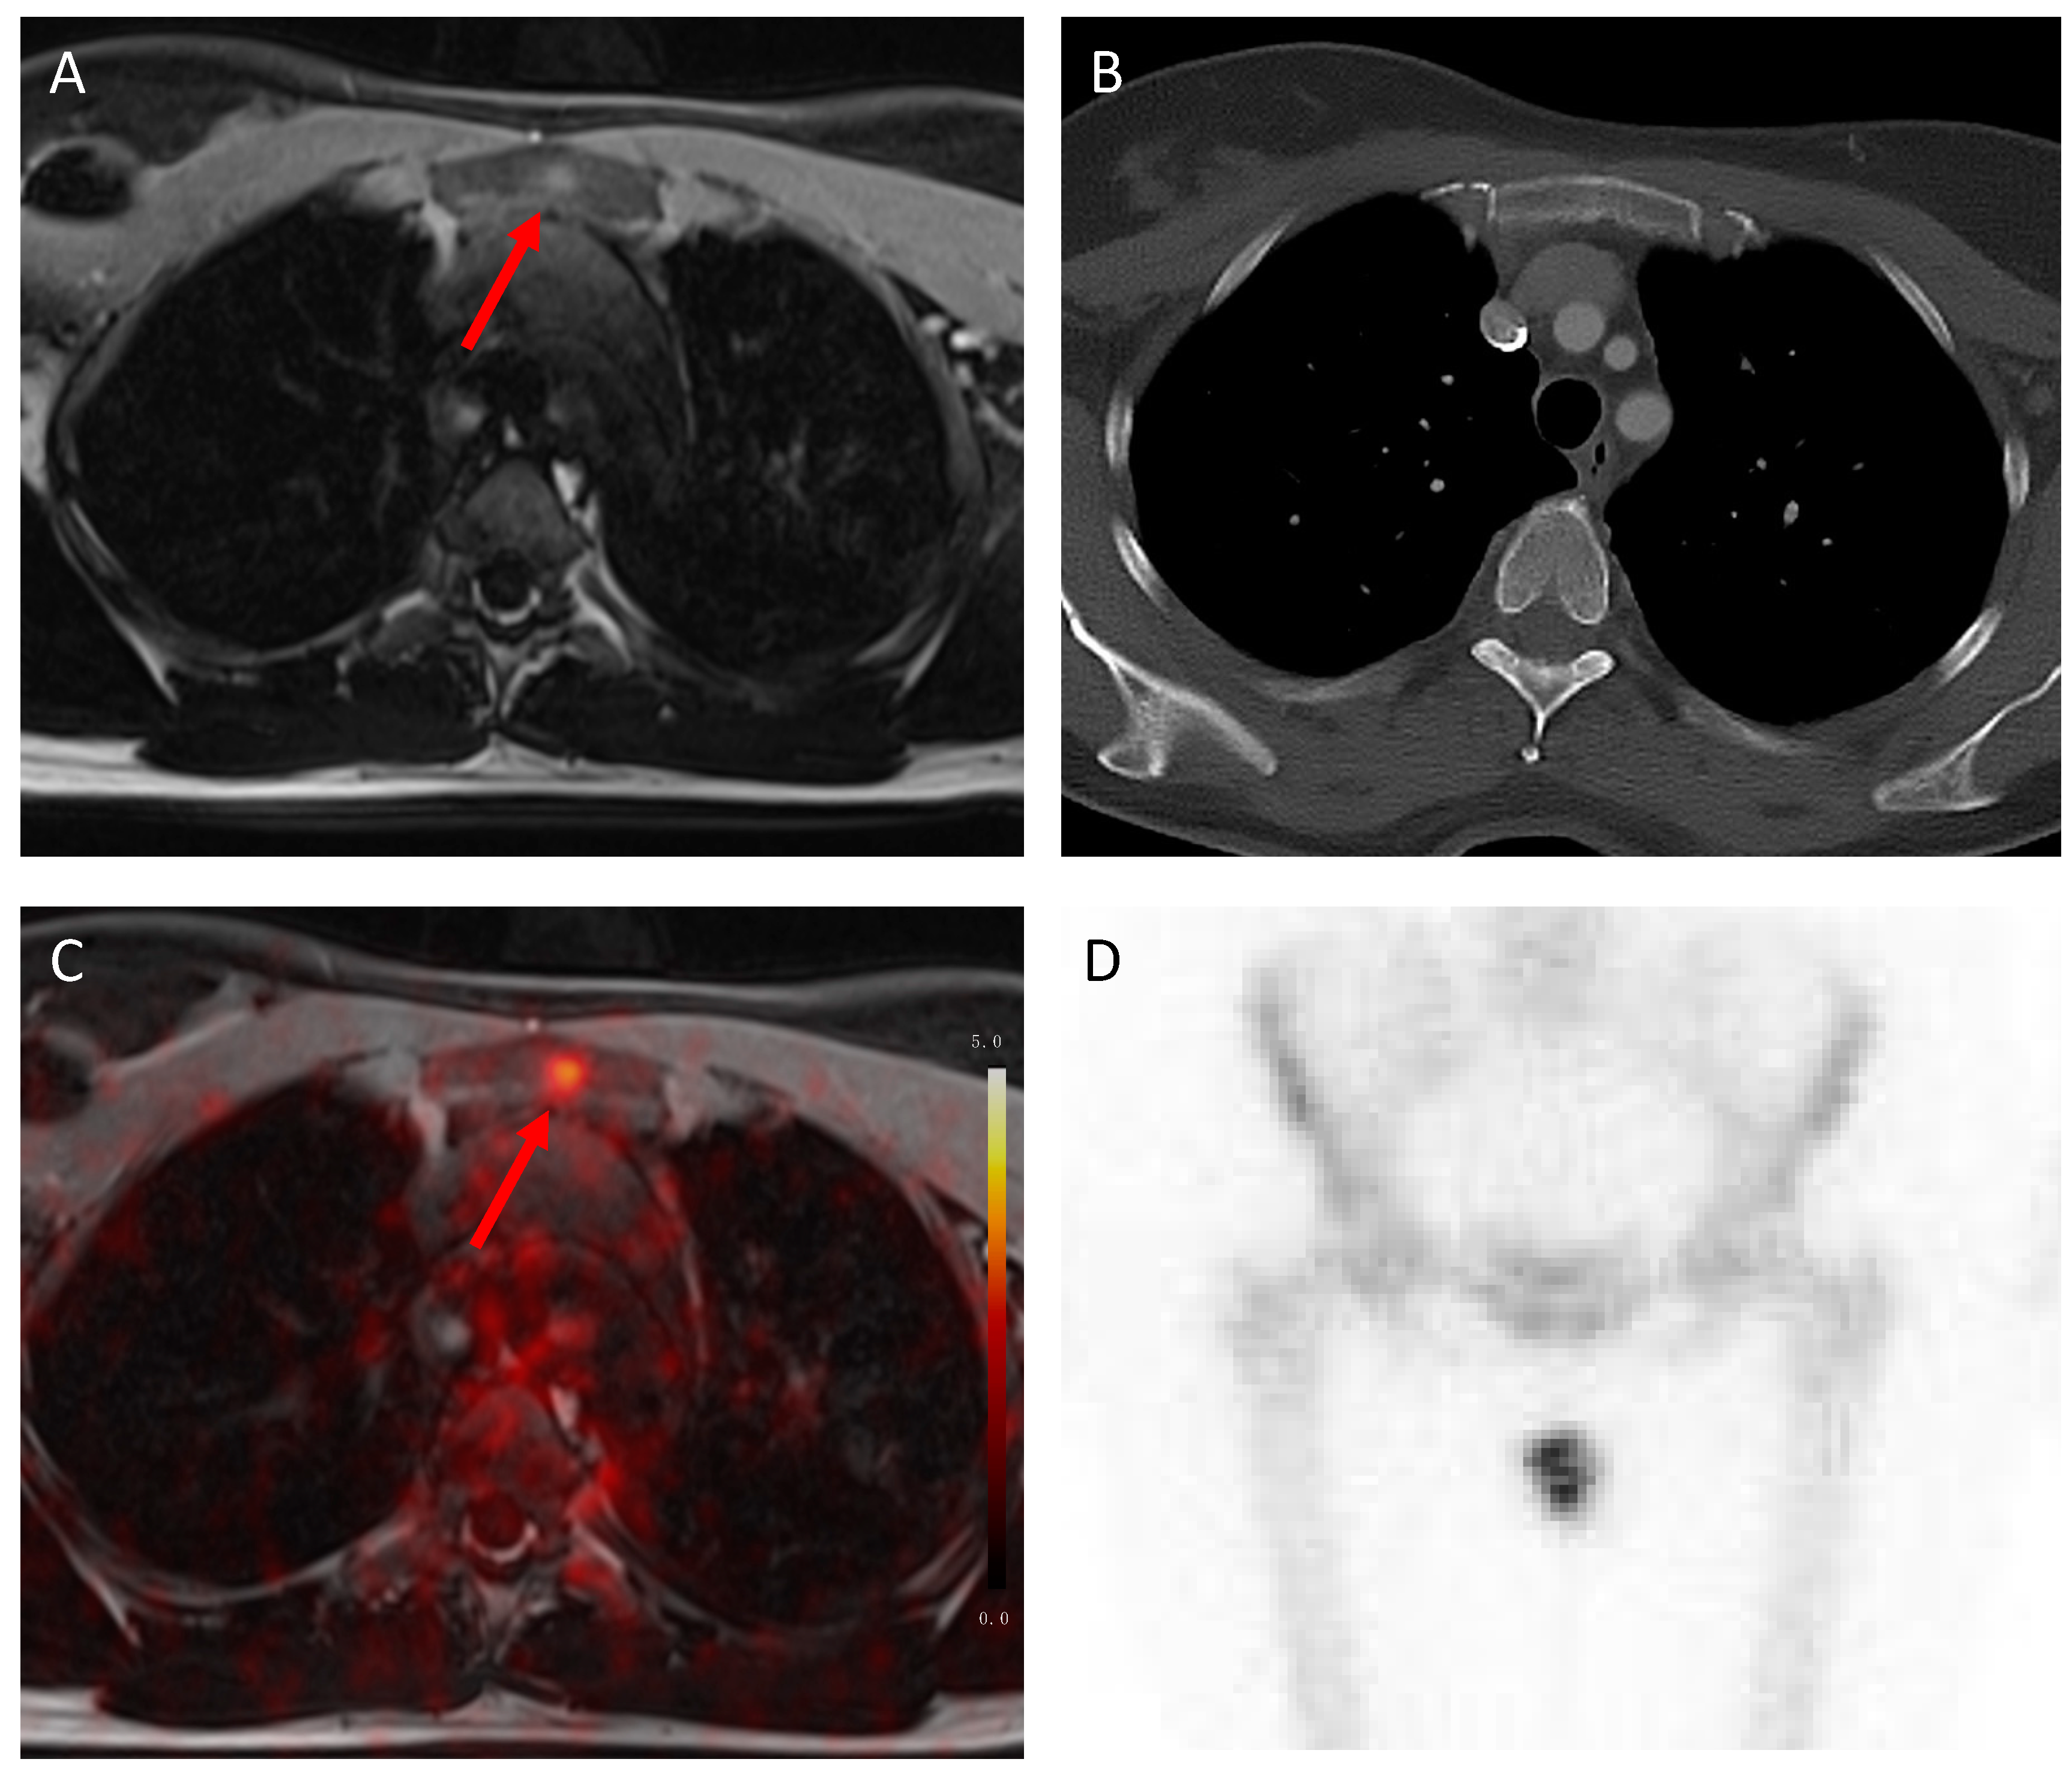

3.2. N Staging

3.3. M Staging